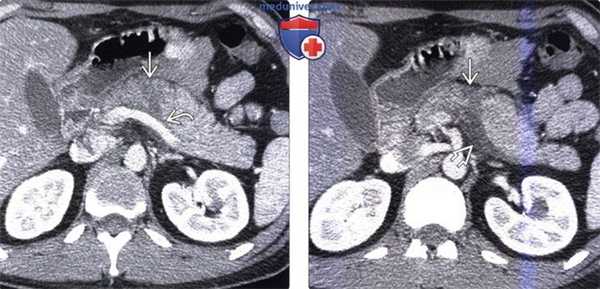

(Слева) На аксиальной КТ с контрастным усилением определяется гиподенсный участок (разрыв) в средних отделах тела поджелудочной железы. Обратите внимание на небольшое количество жидкости позади поджелудочной железы поблизости от селезеночной вены.

(Справа) На аксиальной КТ с контрастным усилением у этого же пациента на более каудальном уровне также определяется разрыв поджелудочной железы; жидкость возле ее края становится более очевидной. У некоторых пациентов наличие жидкости позади поджелудочной железы является наиболее очевидным признаком ее разрыва.